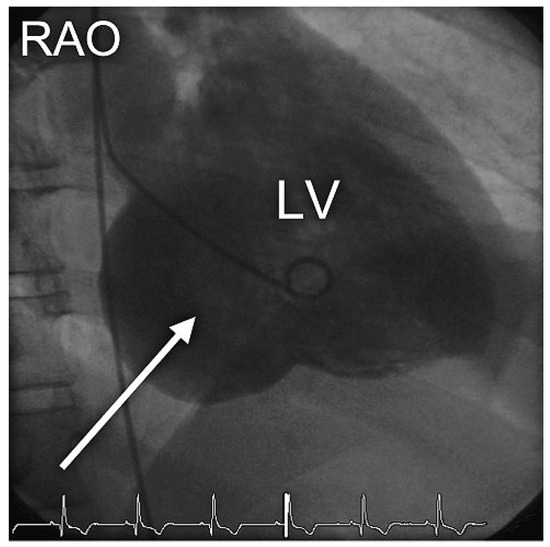

Kammertachykardie aus Substrat

by Richard Kobza and Paul Erne

Cardiovasc. Med. 2009, 12(11), 317; https://doi.org/10.4414/cvm.2009.01458 - 13 Nov 2009

Ein 50-jähriger Patient wird zugewiesen mit Verdacht auf epileptischen Anfall [...] Full article

Show Figures

Figure 1